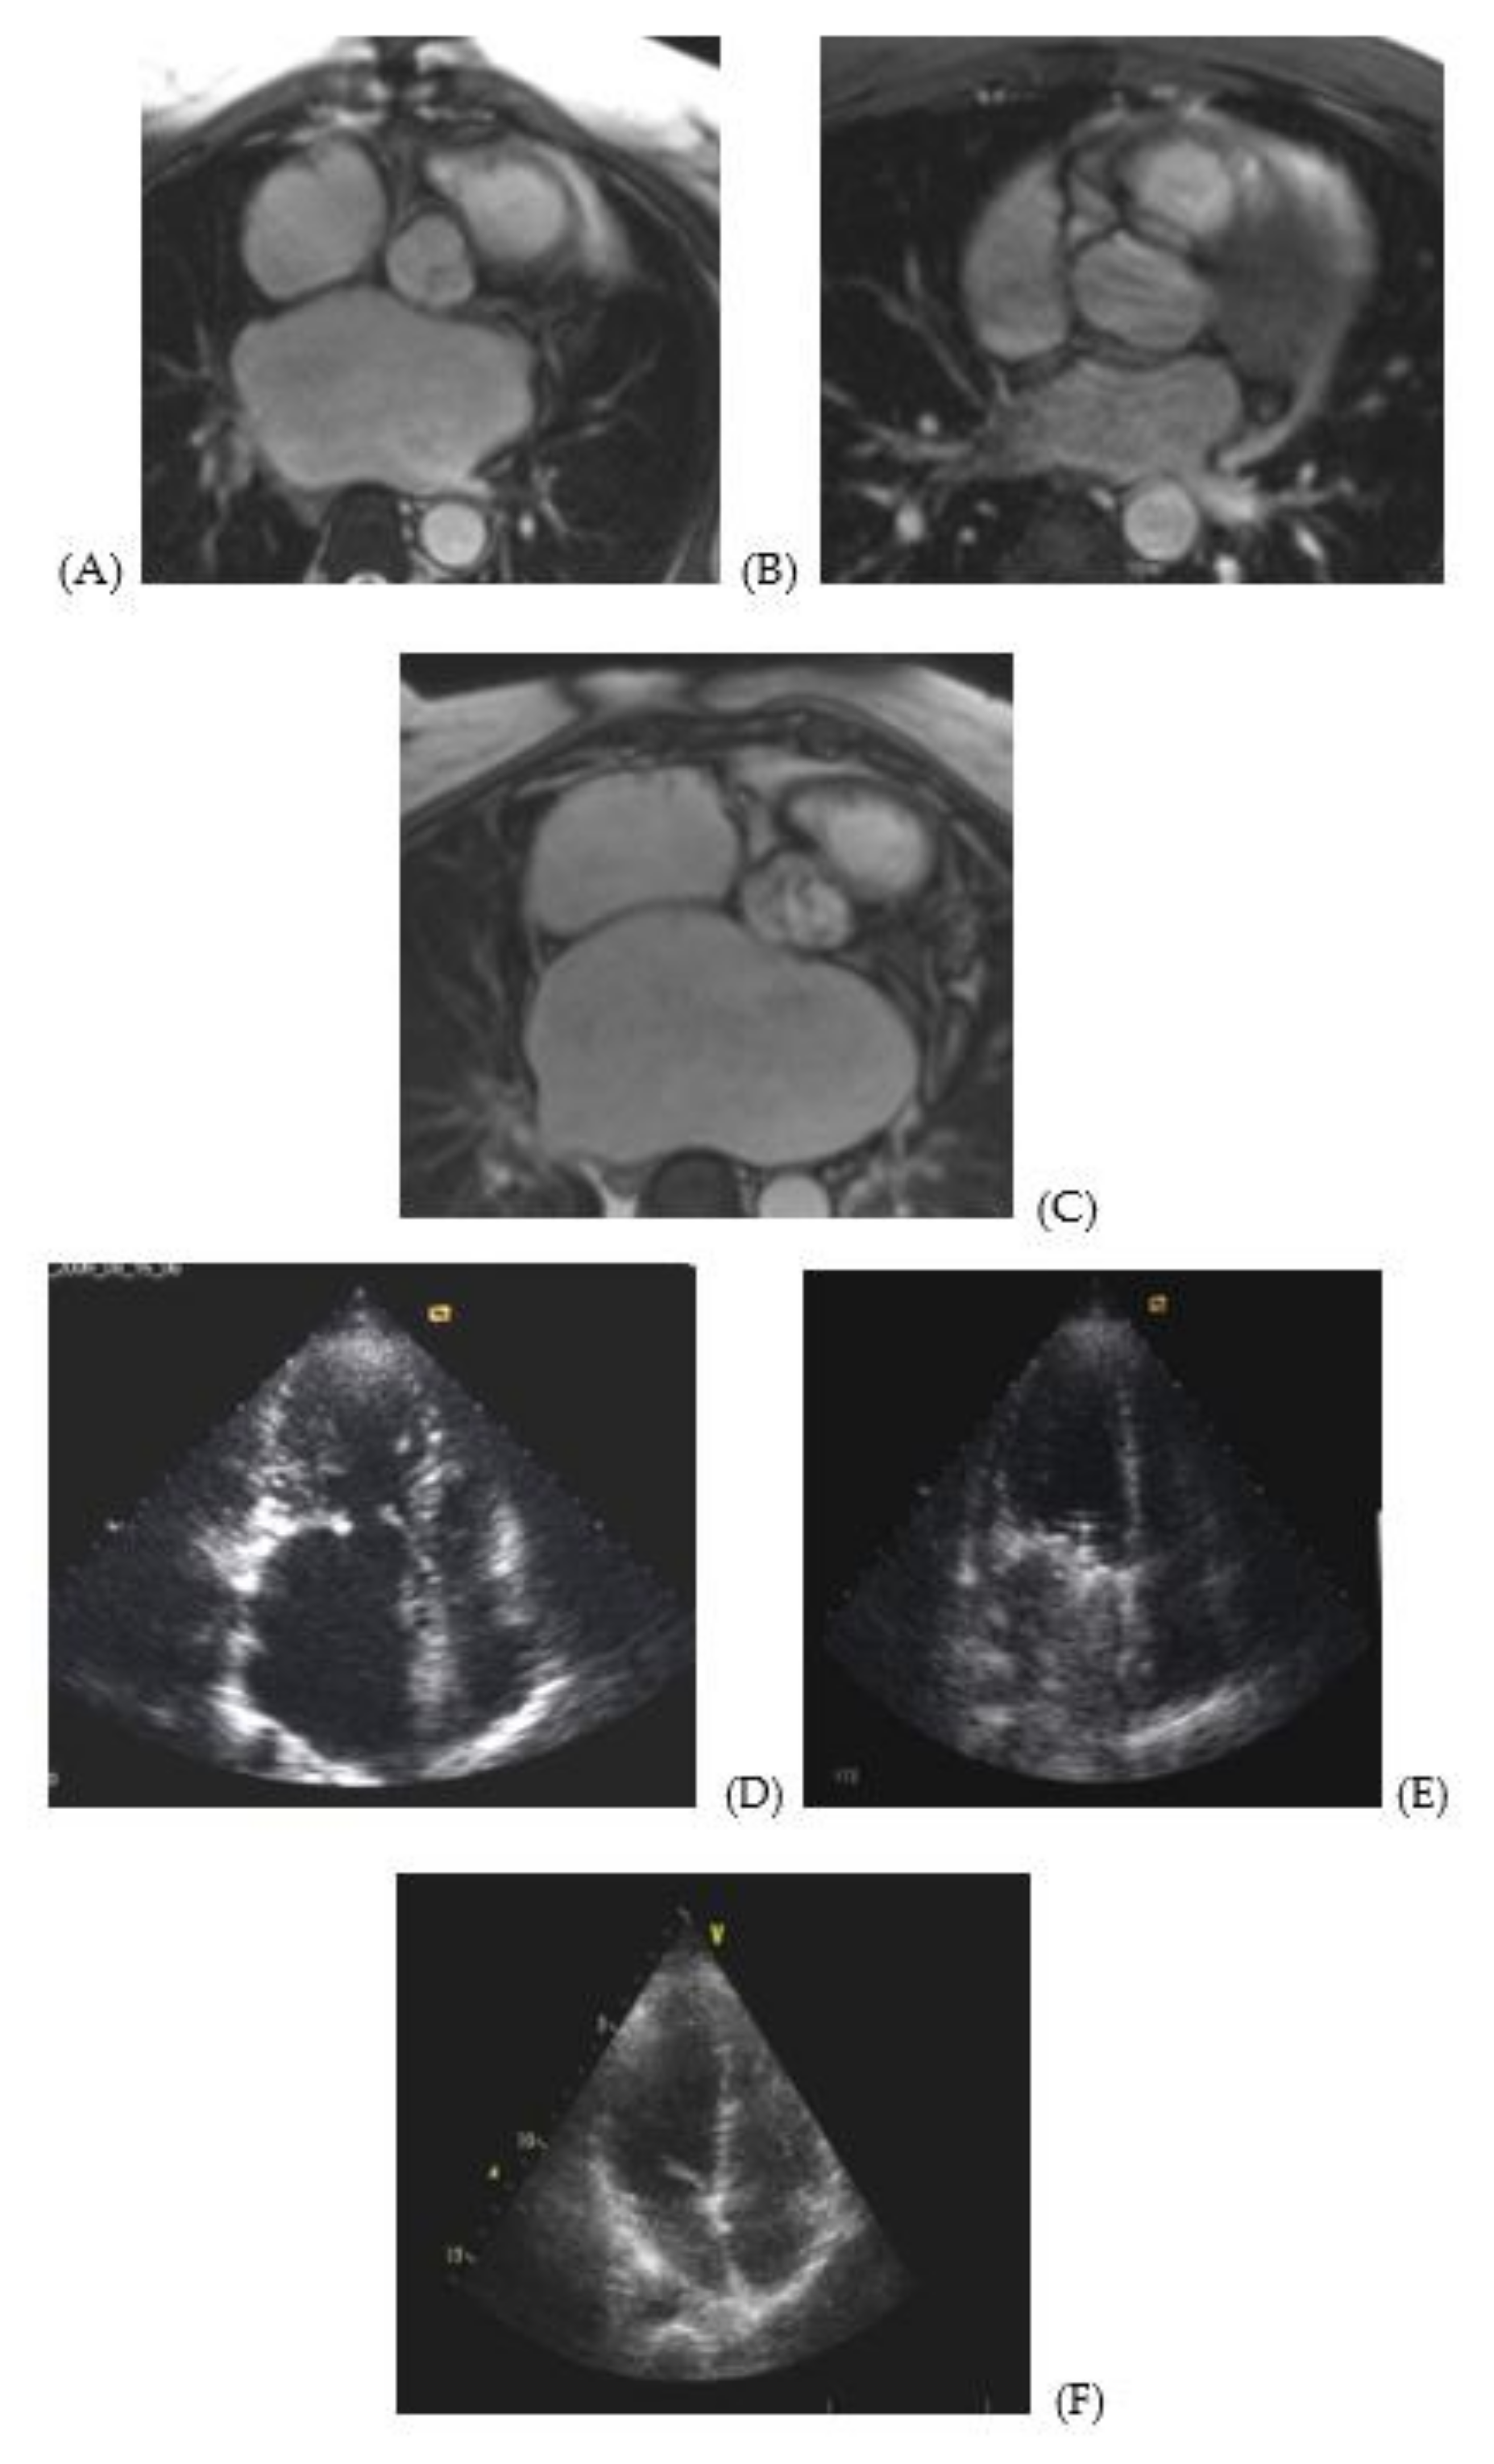

MRI and echocardiographic images (Figure 1) illustrate enlargement and deformation of the atria prior to surgery (Figure 1A,E) as compared to normal volume and shape (Figure 1C,F). Figure 1B,E illustrate a pronounced positive dynamics in remodeling of the atria after surgery. However, atria are not fully restored. At the same time, the left ventricle’s shape and volume are restored almost completely (Figure 1D–F).

Figure 1. MRI and echocardiography images of atria of a 48 year-old male patient with MVD prior to surgery and 5 years later. MRI image of a cross section of the right and left atria at the level of the aortic root of a 48 year-old male patient with stenosis and mitral valve insufficiency (3d degree): (A) prior to surgery, (B) following surgery, (C) normal atria of a patient from the control group. Apical access echo image of the left atrium of a 48 year-old male patient with stenosis and mitral valve insufficiency (3d degree): (D) prior to surgery, (E) following surgery, (F) normal atria of a patient from the control group.